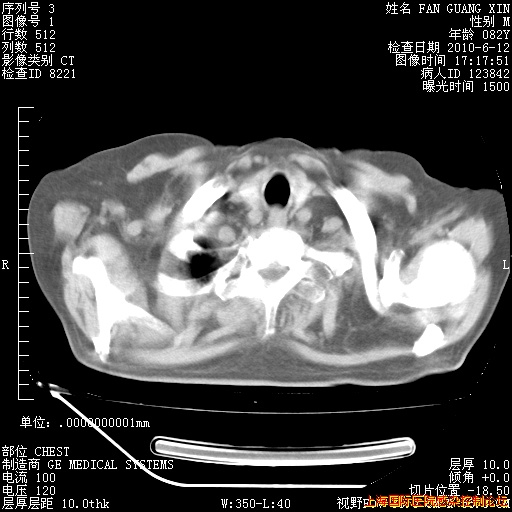

6月12日纵膈窗